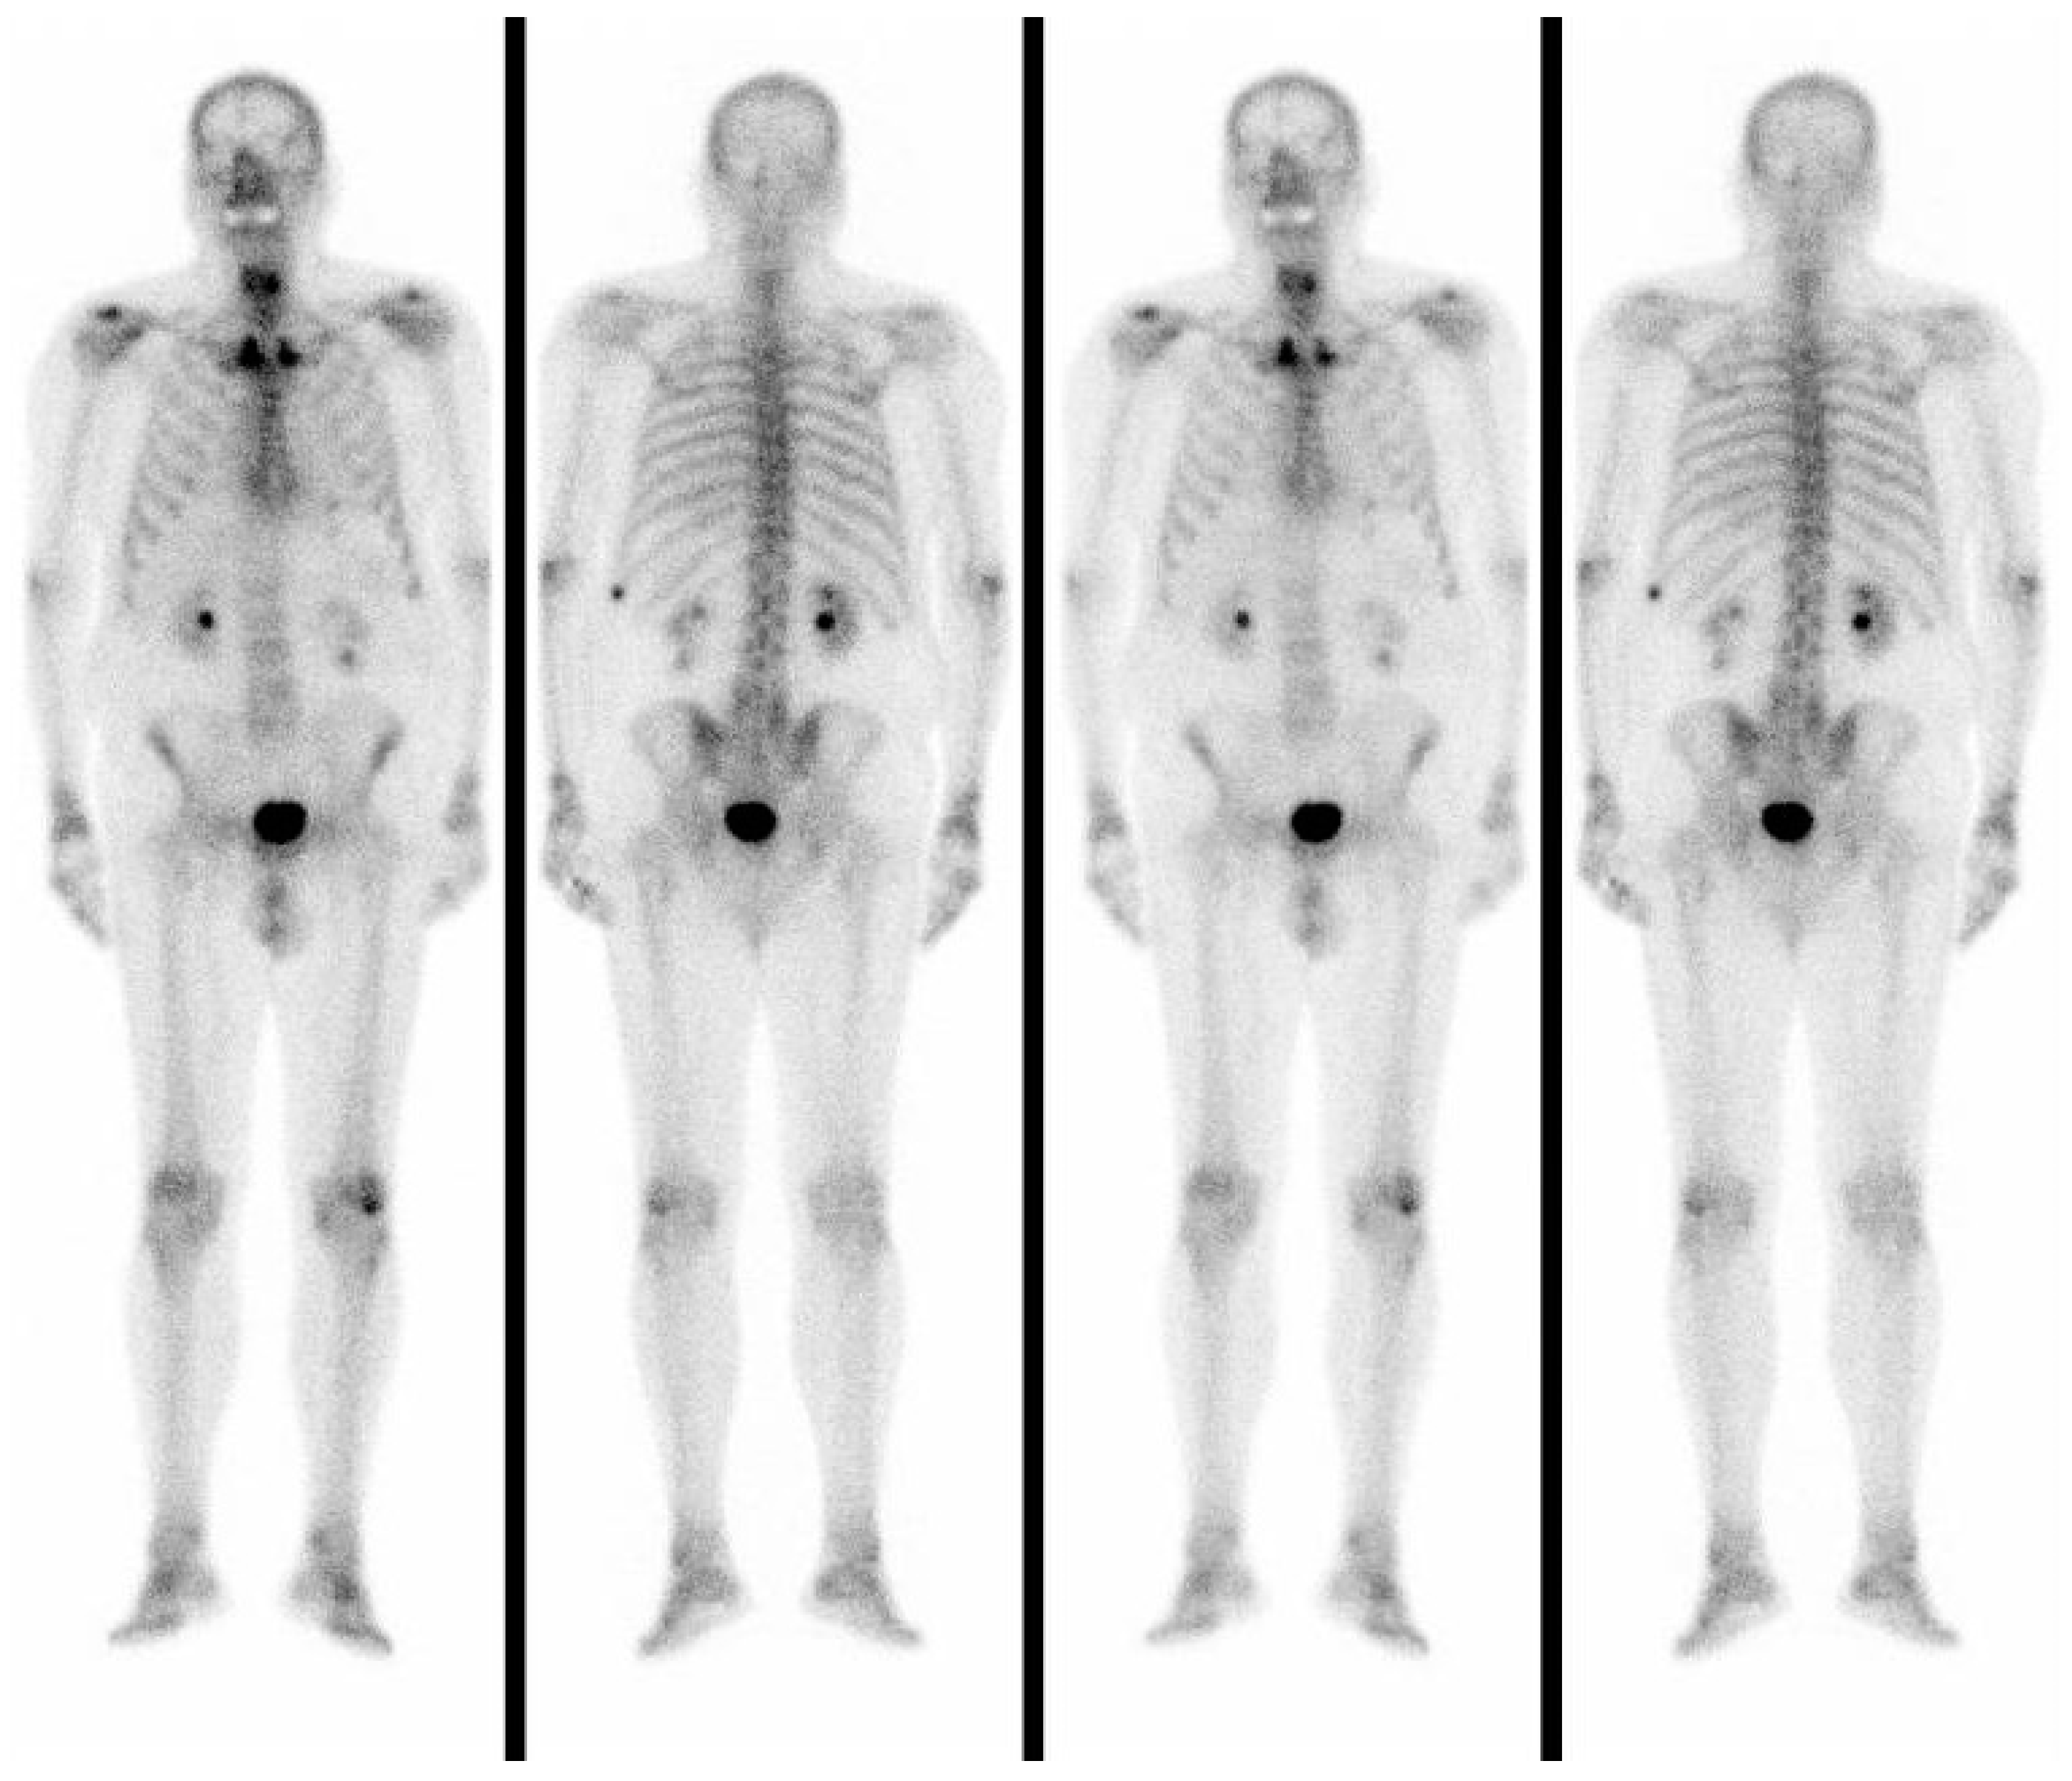

In a total-body bone scintigraphy, the accumulation of 99mTc was not detected in the anterior neck but only in the left X rib, which was the site of a previous fracture (Figure 4).

Figure 4. Total-body bone scintigraphy showing the accumulation of 99 mTc that was not detected in the anterior neck but only in the left X rib which was the site of a previous fracture.